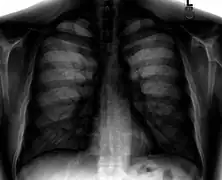

A normal posteroanterior (PA) chest radiograph of someone without any signs of injury. Dx and Sin stand for "right" and "left" respectively.